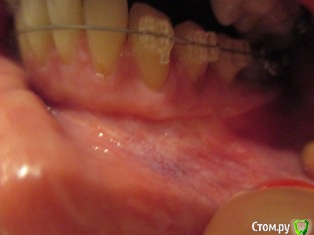

Наталья1 Опубликовано 30 марта, 2017 Автор Поделиться Опубликовано 30 марта, 2017 1) Первые 2 фото - левый нижний сегмент после операции,2) 3 следующих фото - правый нижний сегмент без операции ( требуется ли? ИМХО, разница в высоте прикрепления десны незначительная, а какие последствия на лице!), 3) последнее фото - последствия на лице ( залом на щеке). Ссылка на комментарий